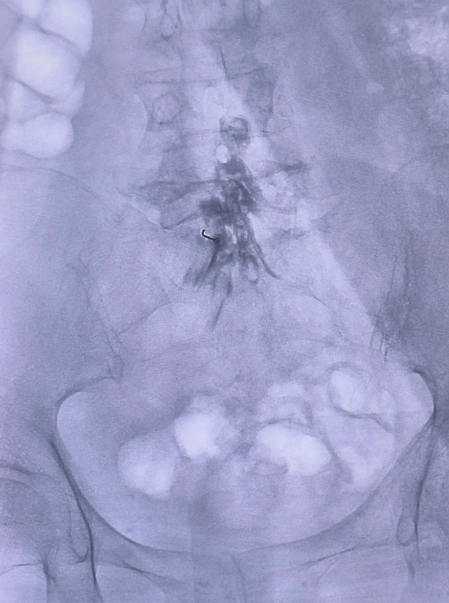

种建超医生接诊后,为张先生进行了详细专业的体格检查和影像学阅片,明确诊断为“腰椎间盘突出症”。考虑到患者强烈的保守治疗意愿及避免大开刀的需求,种医生及其团队经过严谨评估,为张先生制定了个体化的微创治疗方案——在介入室行“胶原酶化学溶盘术”。该技术属于精准介入治疗,通过将特定药物注入突出的椎间盘内,溶解导致压迫的突出物,从而解除对神经根的刺激,达到治疗目的。